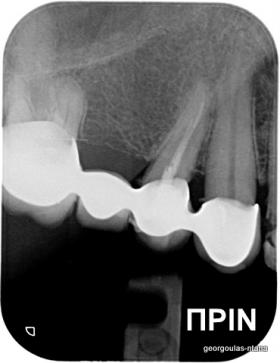

ΟΛΙΚΗ ΑΠΟΚΑΤΑΣΤΑΣΗ ΑΝΩ ΓΝΑΘΟΥ

Η ασθενής ήταν δυσαρεστημένη από την εμφάνιση των άνω δοντιών της. Ήθελε τα δόντια της να αποκτήσουν ομοιόμορφο, πιο λευκό χρώμα κ να αποκτήσει ένα πιο αρμονικό χαμόγελο με φυσική εμφάνιση. Λόγω των εκτεταμένων εμφράξεων σύνθετης ρητίνης στα πρόσθια δόντια, των εμφράξεων αμαλγάματος στα πίσω αριστερά δόντια αλλά και της υπάρχουσας γέφυρας στα πίσω δεξιά δόντια, και σε συνδυασμό με την επιθυμία της ασθενούς για φυσικό αποτέλεσμα αποφασίστηκε η τοποθέτηση ολοκεραμικών στεφανών στα δόντια της άνω γνάθου. Στη θέση του δεύτερου προγομφίου δεξιά τοποθετήθηκε εμφύτευμα. Πραγματοποιήθηκε περιοδοντική θεραπεία, ενδοδοντικές θεραπείες (απονευρώσεις) κ τοποθετήθηκαν ενδορριζικοί άξονες υαλονημάτων  όπου κρίθηκε απαραίτητο. Σε όλη τη διάρκεια της θεραπείας η ασθενής ήταν καλυμμένη αισθητικά κ λειτουργικά με προσωρινές αποκαταστάσεις.